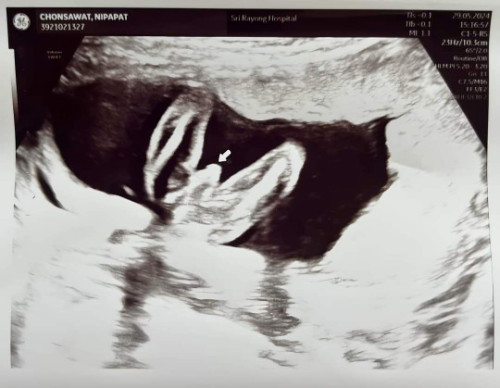

เพศลูก แอบหวังชาย แต่คงไม่หด กลับไปเป็นหญิงนะคะ หมอแจ้งแค่อาจจะ แต่ยังไม่ชัวร์ค่ะ

16วีค แบบนี้ชายหรือหญิงคะแม่ๆ

ชาย100%ค่ะแม่ไม่มีหดแล้ว

บ้านนี้ลูกชายชัดแจ๋วเลยค่ะ

ของเค้าโผล่แบบนี้ ผช ค่ะ

น่าจะชายแล้วนะคะแบบนี้

ชายแน่นอนค่ะแม่